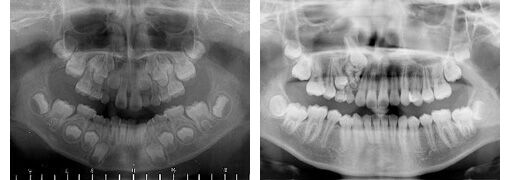

7月2日に現地の病院でCTを撮影したところ、衝撃の事実が発覚した。右の眼窩のすぐ下に楔形の歯があり、今にも眼部に飛び出してきそうな状況だったのだ。

親知らずまで32本全部そろっているように見えるんだが、

一本は乳歯のままなのか。写真左上の糸切り歯がそうかな?。

右上の糸切り歯の場所に乳歯がいすわっていて

中の歯の種みたいな奴が埋まっていて目の方向に向かって生え始めたんだな

ここまで眼窩に近いのは初めて見た

逆生で上顎内にあるのはよく見るけど

右上Cが残っていて、右上3番が逆生しとるんだな

てか、この人、左上3と4の間にも何かない?